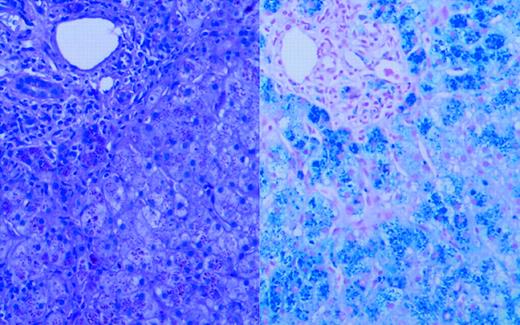

Liver biopsy. See the complete figure in the article beginning on page 2176.